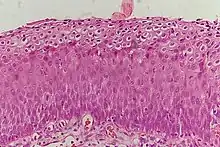

Normal cervical epithelium

Historically, abnormal changes of cervical epithelial cells were described as mild, moderate, or severe epithelial dysplasia. In 1988 the National Cancer Institute developed "The Bethesda System for Reporting Cervical/Vaginal Cytologic Diagnoses".[12] This system provides a uniform way to describe abnormal epithelial cells and determine specimen quality, thus providing clear guidance for clinical management. These abnormalities were classified as squamous or glandular and then further classified by the stage of dysplasia: atypical cells, mild, moderate, severe, and carcinoma.[13]

Depending on several factors and the location of the lesion, CIN can start in any of the three stages and can either progress or regress.[1] The grade of squamous intraepithelial lesion can vary.

CIN is classified in grades:[14]

Histology Grade Corresponding Cytology Description Image

CIN 1 (Grade I) Low-grade squamous intraepithelial lesion (LSIL)

• Mild epithelial dysplasia

• Confined to the basal 1/3 of the epithelium

• Typically corresponds to infection with HPV

• High rate of regression back to normal cells

• Usually managed expectantly

CIN 2/3 High-grade squamous intraepithelial lesion (HSIL)

• Represents a mix of low- and high-grade lesions not easily differentiated by histology

• HSIL+ encompasses HSIL, AGC, and cancer

CIN 2 (Grade II)

• Moderate dysplasia confined to the basal 2/3 of the epithelium

• CIN 2+ encompasses CIN 2, CIN 3, adenocarcinoma in situ (AIS), and cancer

CIN 3 (Grade III)

• Severe dysplasia with undifferentiated neoplastic cells that span more than 2/3 of the epithelium

• May involve the full thickness

• May also be referred to as cervical carcinoma in situ

• CIN 3+ encompasses CIN 3, AIS, and cancer